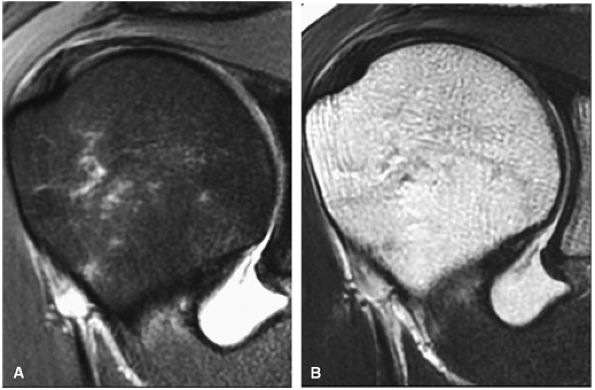

FIGURE 8.2 ● Rotator cuff tendon on coronal FS PD FSE (A) and T2 FSE (B) images using an eight-channel phased-array coil.